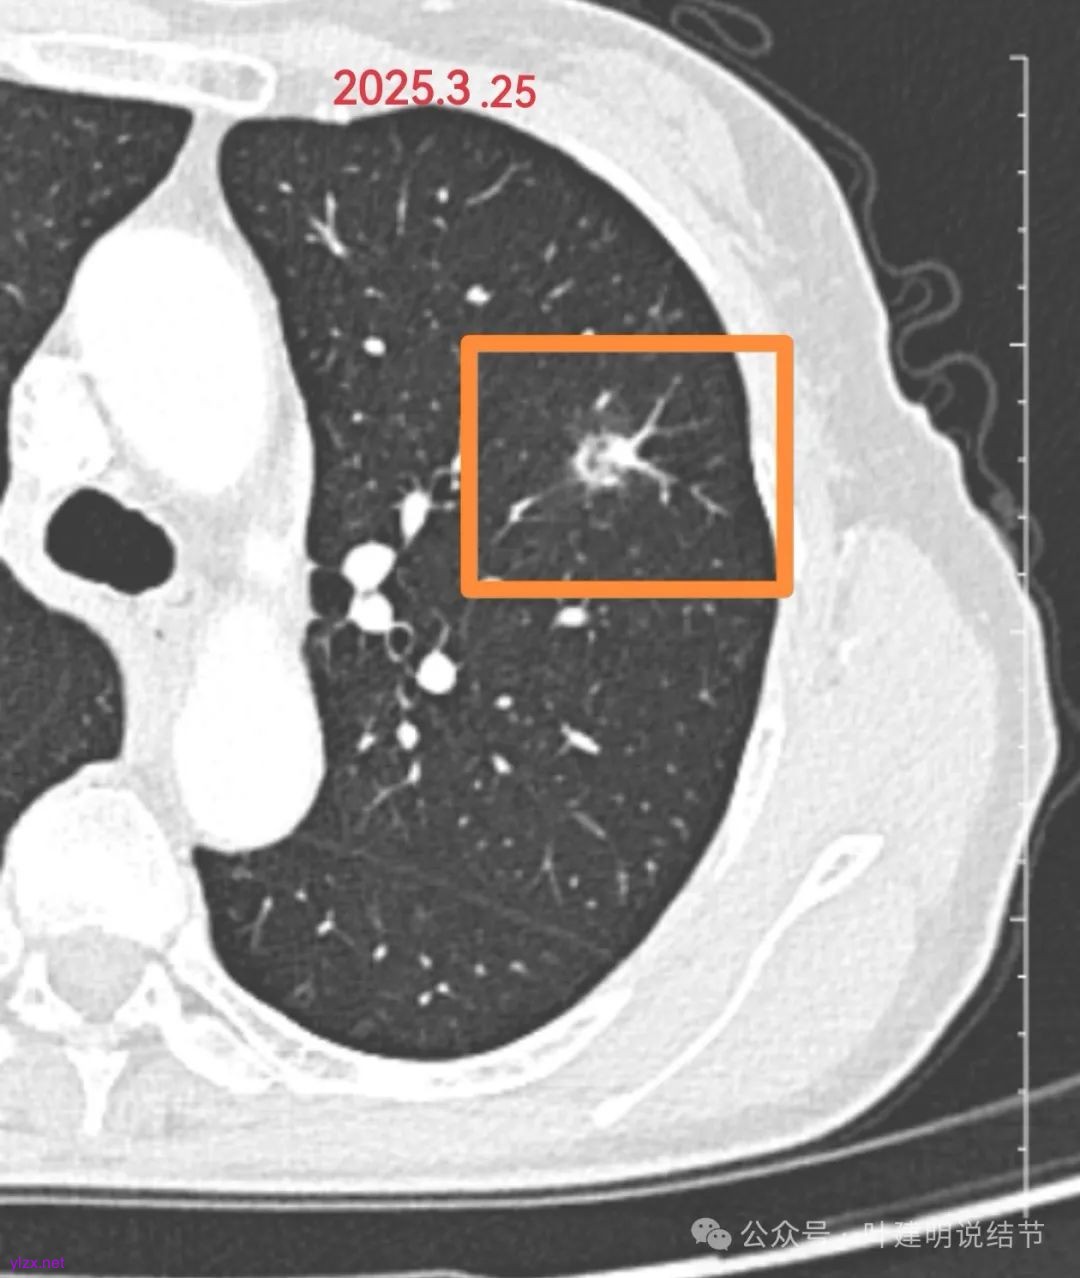

上图是2025年3月复查的,大约一个月的时间,病灶密度明显减低,中间出现了空泡样的影像。说明病灶已经明显吸收好转,是没有完全吸收光而已。